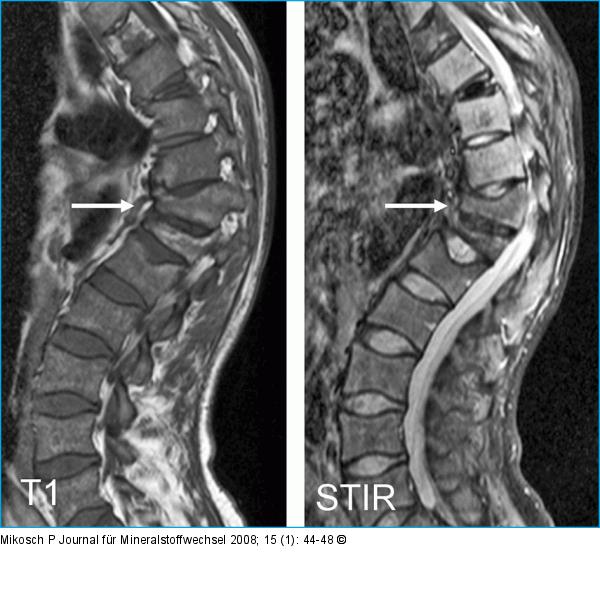

Abbildung 3: Wirbelkörperfraktur MRI T1 und STIR Wirbelsäule: Wirbelkörperfrakturen Th11 und Th 12 mit Kyphoseknick (Pfeil). Verminderte Signale der Wirbelkörper in den T1- und STIRSequenzen typisch für ausgedehnte Markinfiltration bei Mb. Gaucher. |